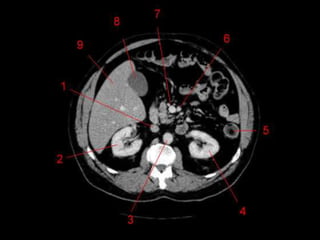

Subdivisão Funcional • Osoito segmentos são divididos: – A primeira divisão é realizada dividindo através da Porta Hepática, em esquerdo (I a IV) e direito (V a VIII) – A divisão é feita baseada em um relógio – Caudado é o segmento I – No ‘lobo’ esquerdo, o IV separa-se do II e do III pela veia hepática esquerda, representado anatomicamente pelo ligamento falciforme. – II e III se dividem através de uma linha imaginária transversal na altura da porta hepática. – No ‘lobo’ direito, se divide os segmentos através de uma linha transversal e pela veia hepática direita.

Subdivisão Funcional • Fundamentalimportância para Ressecção. • Maioria das lesões são do fígado direito.